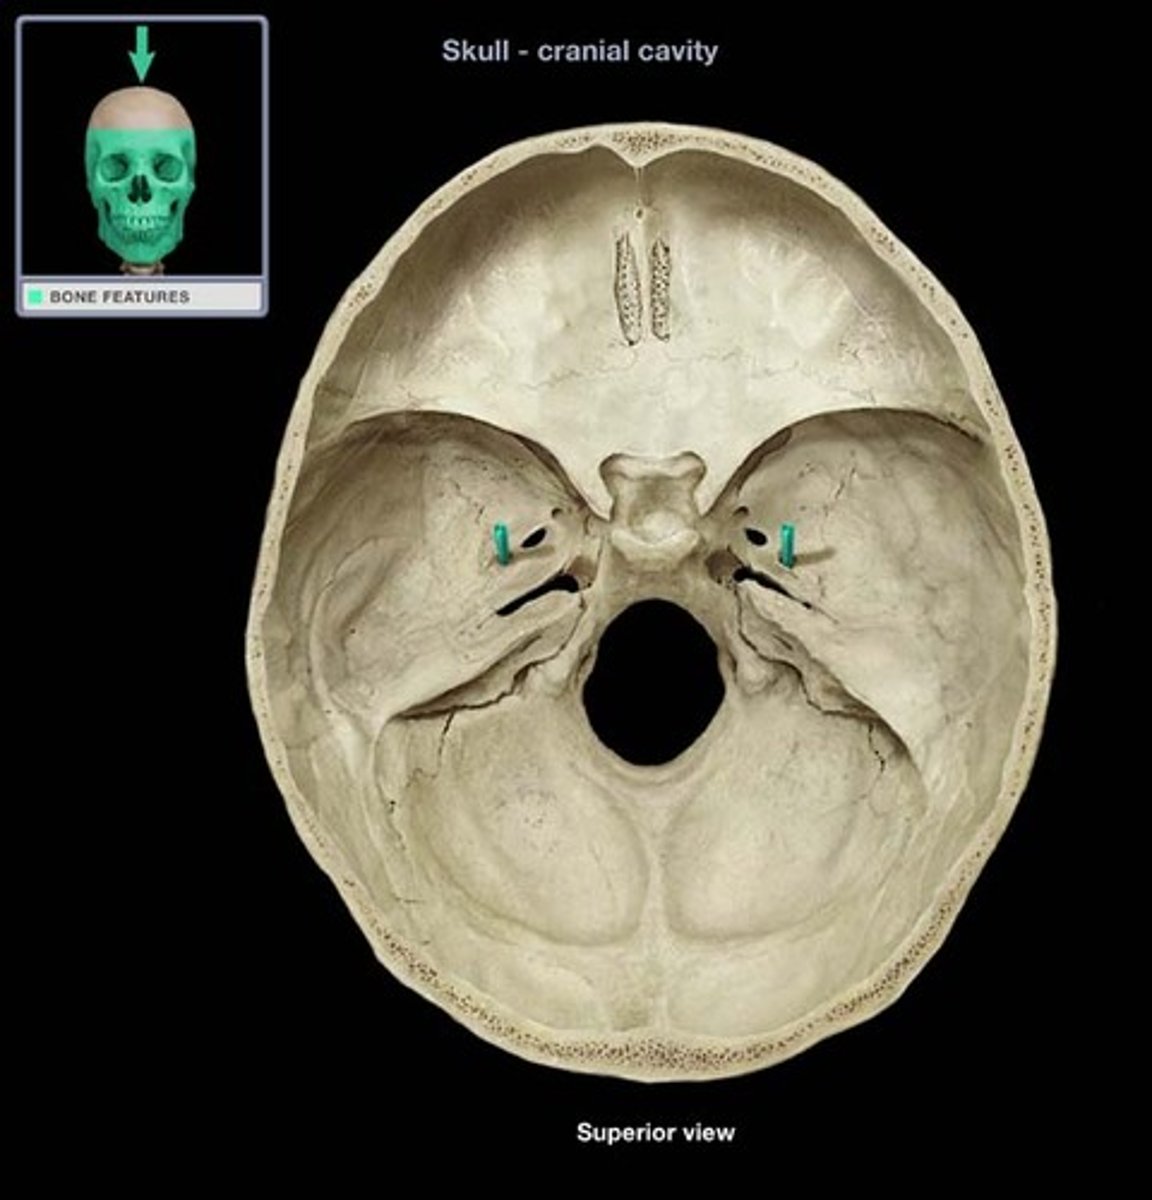

Petrous region

Includes the internal acoustic meatus/internal auditory canal